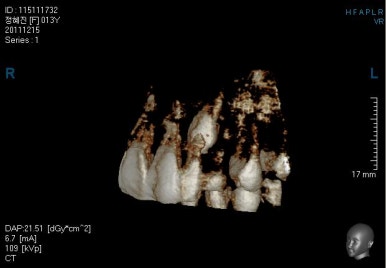

그 다음 문제는 왼쪽 송곳니 부분(붉은색 동그라미)이 유치가 남아있고, 영구치가 매복되어 있는 경우였어요.

화살표를 보시면 송곳니가 나오지 못하고 뼈속에 묻혀 있는 것을 볼 수 있습니다.

이를 "매복치" 혹은 "매복치아" 라고 표현하는데 이넞ㅂ한 치아들의 뿌리를 녹인다거나 아예 다른 방향으로 간다거나 하는 문제가 생길 수 있기 때문에 조기에 발견하고 치료를 해줘야 합니다.

상태를 보면 옆에 있는 안그래도 작은 왜소치의 뿌리를 건드리는 양상으로 있어서 좀 더 정밀한 3차원 CT를 찍어 보기로 했습니다.

이렇게 정확한 위치를 파악해보니 다행히 인접한 치아에 안좋은 영향을 주고 있는 것은 아니었고 어부바처럼 겹쳐있기만 했어요.